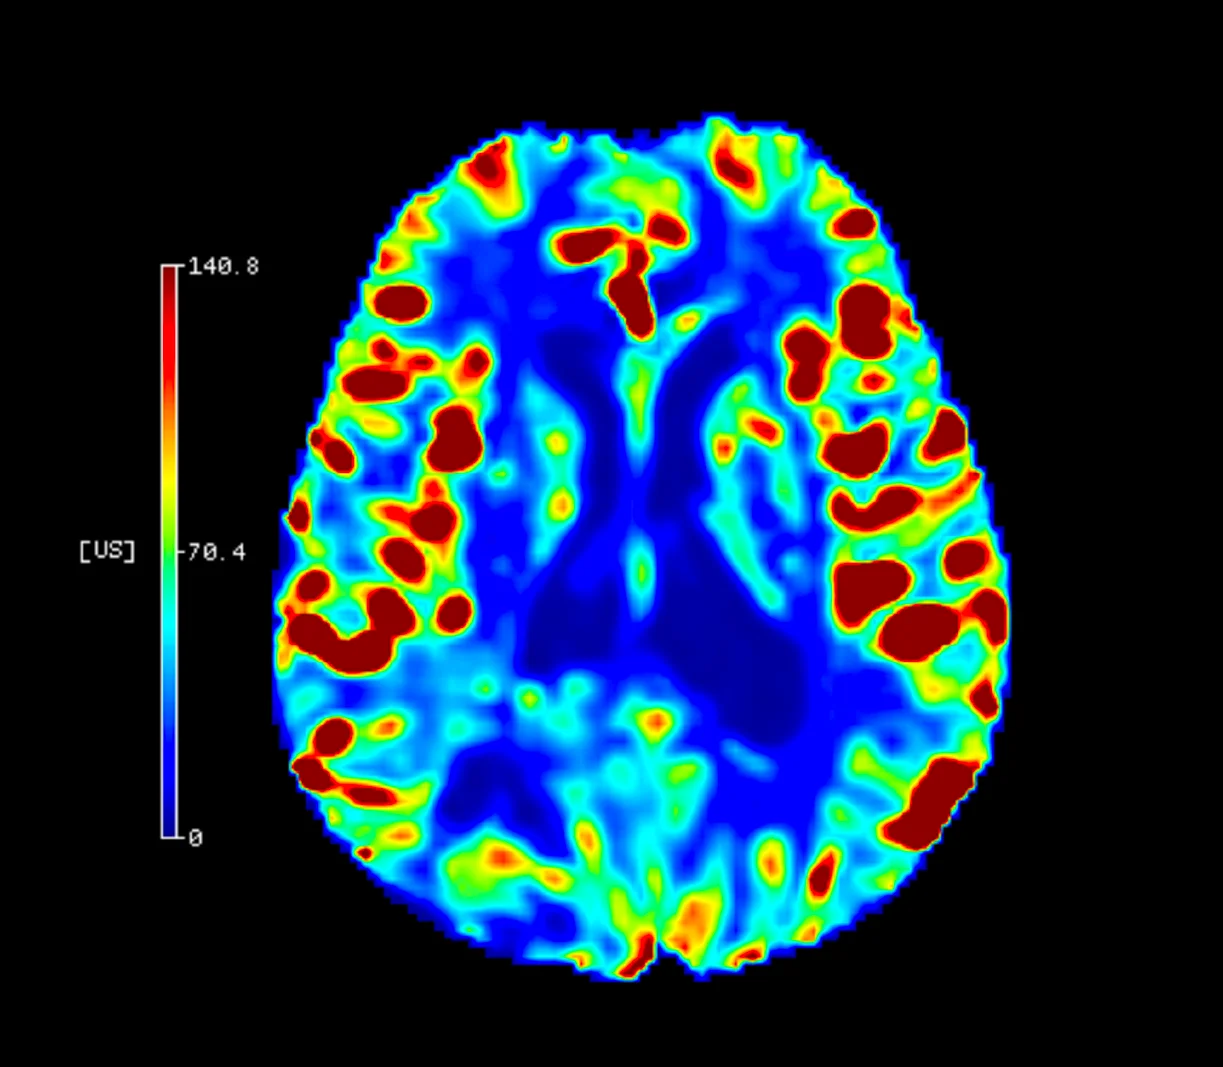

Eşik Değer Tabanlı Lezyon Kantifikasyonu

Cercare Medical Neurosuite Stroke yazılımının gelişmiş paketinde yer alan eşik değer tabanlı lezyon kantifikasyonu, perfüzyon parametrelerinin belirlenmiş klinik eşik değerlerle karşılaştırılması yoluyla çalışır. Özellikle Tmax, CBF ve CBV gibi parametreler için literatürde yaygın olarak kabul gören cut-off değerleri kullanılarak, çekirdek infarkt (geri dönüşsüz doku) ve penumbra (kurtarılabilir doku) hacimleri sayısal olarak hesaplanır.

Bu kantifikasyon sayesinde radyolog ve nörologlar, lezyon boyutunu ve konumunu mililitre (mL) cinsinden objektif bir şekilde değerlendirebilir. Klinik araştırmalar, bu yöntemle elde edilen kantitatif analizlerin, görsel yorumlamaya kıyasla hasta seçiminde tutarlılığı %25’e kadar artırdığını ve tedaviye uygunluk kararlarını hızlandırdığını göstermektedir*.

AI Tabanlı Lezyon Kantifikasyonu

Cercare Medical Neurosuite Stroke yazılımının Gelişmiş (Advanced) paketi, yapay zeka destekli algoritmalar ile lezyon kantifikasyonu sağlar. Derin öğrenme tabanlı modeller, binlerce hasta verisi üzerinden eğitilmiş olup, perfüzyon haritalarındaki doku değişimlerini otomatik olarak sınıflandırır. Böylece çekirdek infarkt (geri dönüşsüz doku) ve penumbra (kurtarılabilir doku) ayrımı, yalnızca eşik değer tabanlı hesaplamalara değil, çok boyutlu yapay zeka analizine dayanır.

AI tabanlı sistem, özellikle karmaşık vakalarda ve atipik perfüzyon paternlerinde, hekimlere daha güvenilir kantitatif veriler sunar. Klinik veriler, yapay zekâ destekli analizlerin tedaviye uygun hasta seçiminde doğruluğu %30’a kadar artırdığını ve gözden kaçan küçük lezyonların %20 daha fazla saptanabildiğini göstermektedir*.

Bu yaklaşım, yalnızca görüntüleme parametrelerini değil, aynı zamanda çoklu biyomarker kombinasyonlarını da analiz ederek tedavi kararlarının hızlanmasını sağlar.